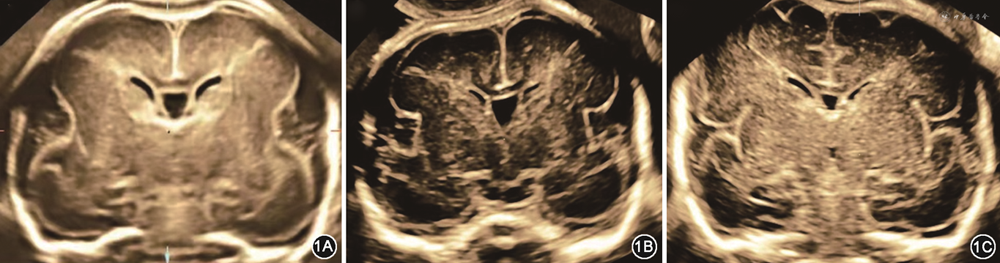

大脑外侧裂是脑皮质发育的一个重要标志,其形态在整个孕期会随着脑皮质发育而改变,是脑皮质发育的里程碑式的标志。根据文献报道[5]及临床观察,孕18周左右冠状切面上大脑外侧裂呈浅弧形;随着孕周进展,弧形逐渐向内加深;孕25周左右呈方形,孕30周左右时呈“π”形;足月时大脑外侧裂逐步完全闭合(图1)。Pooh等[6]在2019年回顾了22例通过尸检、产前MRI或死胎MRI检查证实为MCD胎儿的产前超声表现,提出大脑外侧裂角度较相应孕周的正常胎儿增加是MCD的超声征象。也有研究认为,胎儿大脑外侧裂形态异常是MCD重要的产前影像学征象[7]。目前国内缺乏胎儿大脑外侧裂形态异常与MCD的相关研究。当产前发现胎儿大脑外侧裂形态异常时,胎儿是否有明确的基因异常,是否可以明确诊断MCD,是目前临床亟待解决的问题。本研究收集了本院产前超声发现大脑外侧裂形态异常的胎儿的影像学资料及基因检测结果,拟分析大脑外侧裂异常与MCD的关系,以进一步指导临床实践。